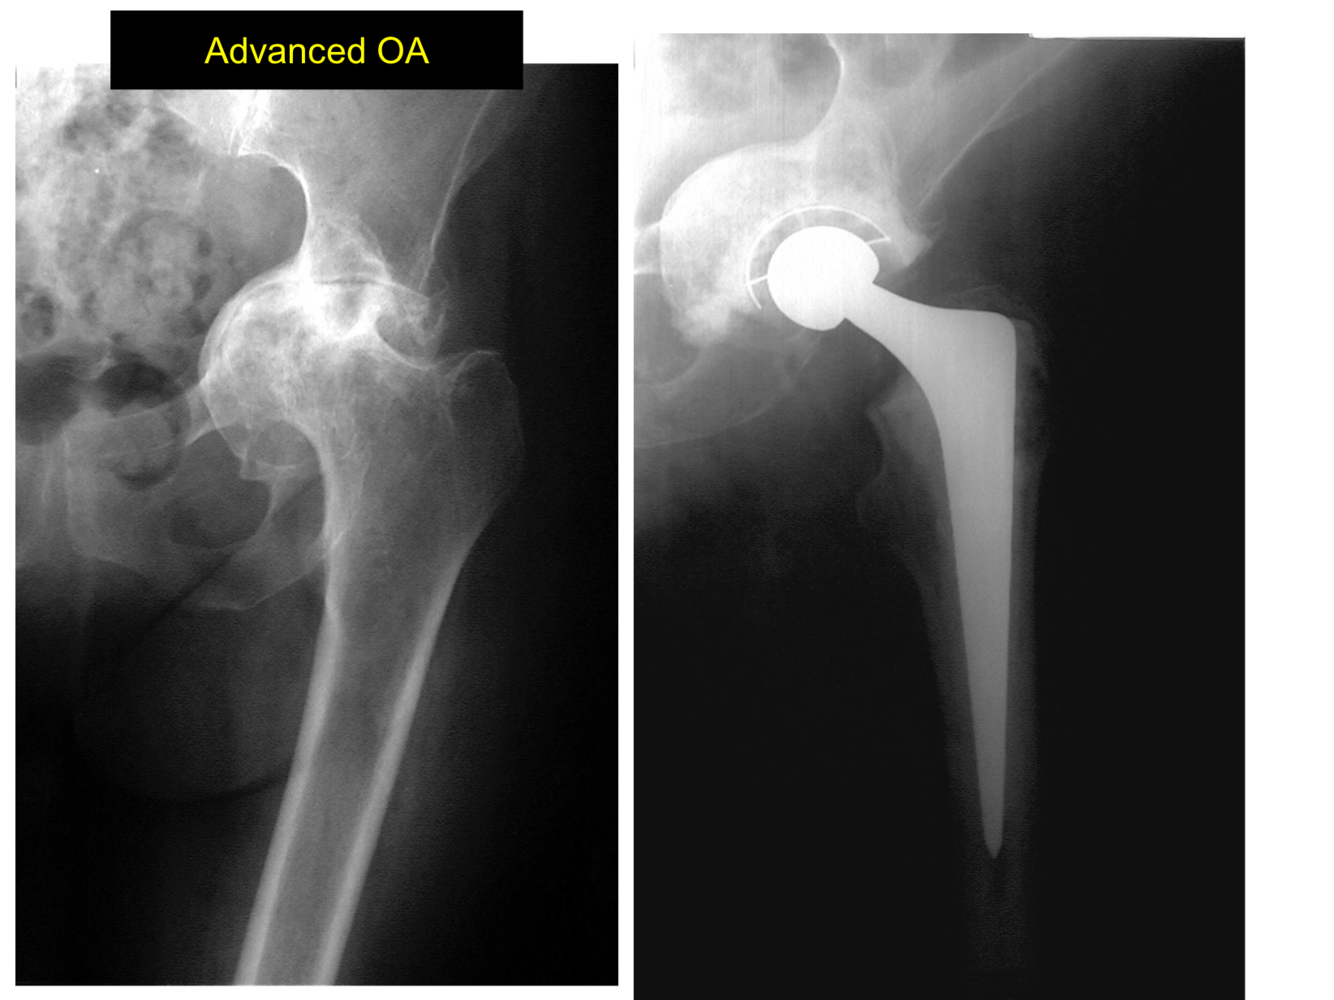

What can be seen on this Xray?